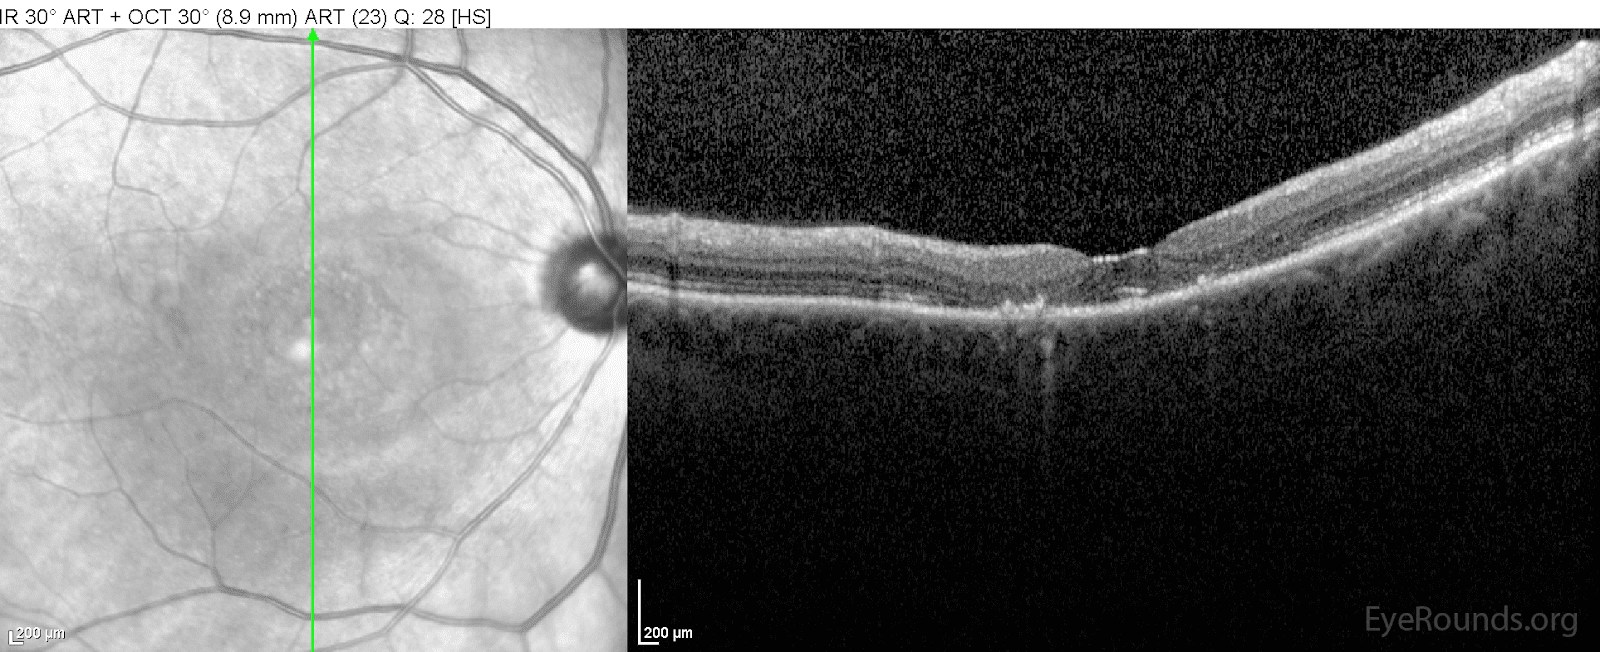

From webeye.ophth.uiowa.edu

Bull'seye maculopathy due to hydroxychloroquine toxicity What Does Hydroxychloroquine Do To Your Eyes This medication may cause serious skin reactions. Tell your care team right away if you have any change in your eyesight. Plaquenil lowers your immune system’s ability to cause inflammation. Hydroxychloroquine (plaquenil) and chloroquine cause ocular toxicity to various parts of the eye such as the cornea, ciliary body, and retina. This can help control symptoms like rashes, skin and.. What Does Hydroxychloroquine Do To Your Eyes.